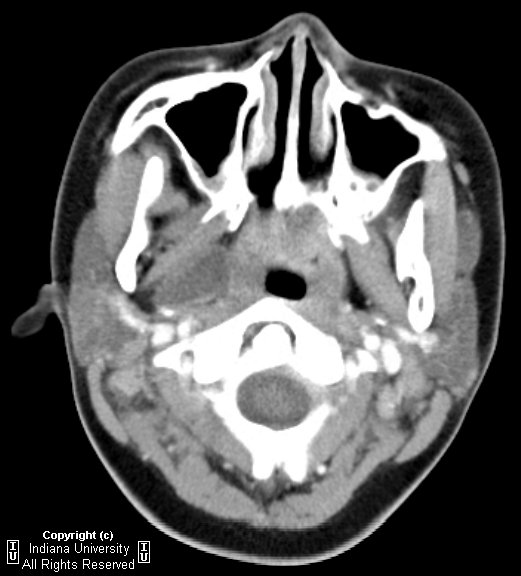

Parapharyngeal abscess, CT scan, axial projection. Download What Is Parapharyngeal Abscess Symptoms include fever, sore throat, odynophagia, and swelling in the neck down. Web a parapharyngeal abscess is a painful collection of pus found within the deep neck space known as the parapharyngeal. Symptoms include fever, sore throat, odynophagia, and swelling in the neck down. Web parapharyngeal abscesses are deep neck abscesses involving the parapharyngeal space. The diagnosis is both clinical. What Is Parapharyngeal Abscess.

CT scan of head axial view showing right parapharyngeal abscess What Is Parapharyngeal Abscess Web a parapharyngeal abscess is a deep neck abscess. The diagnosis is both clinical and. Web parapharyngeal abscesses are deep neck abscesses involving the parapharyngeal space. Web a parapharyngeal abscess is a deep neck abscess. Web parapharyngeal abscess (ppa) refers to a collection of pus located laterally or posteriorly to the pharyngeal constrictor. Symptoms include fever, sore throat, odynophagia, and. What Is Parapharyngeal Abscess.